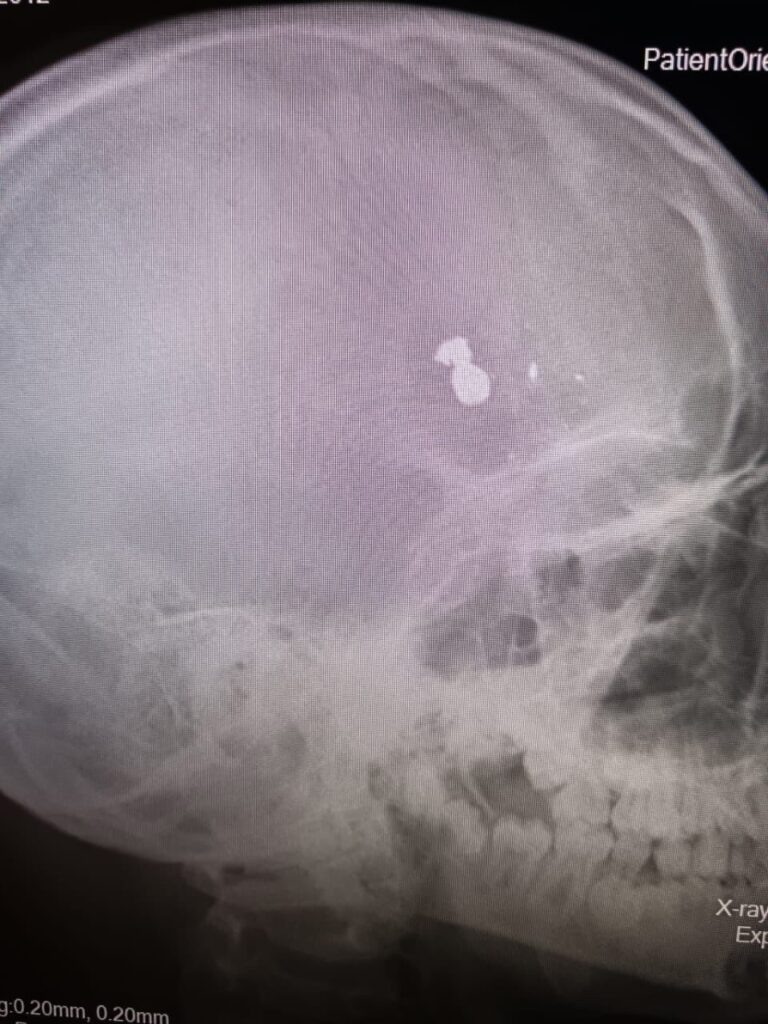

В Дергачевскую районную больницу был доставлен 12-летний мальчик, который при невыясненных обстоятельствах, получил огнестрельное ранение головы. Он был доставлен в детскую областную больницу, где операционная бригада незамедлительно приступила к операции, которая длилась около пяти часов. Об этом сообщило министерство здравоохранения саратовской области и опубликовало фото.

«В результате операции инородные тела (пуля с осколками) удалены. Тяжесть соответствует объёму проведенной операции, оперативное лечение выполнено в полном объёме, проводится наблюдение за ребенком. На данный момент мальчик пришел в сознание. Пожелаем ему скорейшей стабилизации состояния и выздоровления, а всем врачам Дергачевской районной больницы и Саратовской областной детской клинической больницы, принимавшим участие в оказании помощи и продолжающим это делать, спасибо! Так держать! Ваши молниеносные и слаженные действия сработали на результат», — прокомментировал министр здравоохранения Владимир Дудаков. Ерш

«В результате операции инородные тела (пуля с осколками) удалены. Тяжесть соответствует объёму проведенной операции, оперативное лечение выполнено в полном объёме, проводится наблюдение за ребенком. На данный момент мальчик пришел в сознание. Пожелаем ему скорейшей стабилизации состояния и выздоровления, а всем врачам Дергачевской районной больницы и Саратовской областной детской клинической больницы, принимавшим участие в оказании помощи и продолжающим это делать, спасибо! Так держать! Ваши молниеносные и слаженные действия сработали на результат», — прокомментировал министр здравоохранения Владимир Дудаков.

Ершовским межрайонным следственным отделом следственного управления СК России по Саратовской области проводится процессуальная проверка. Предварительно установлено, что 8 ноября 2024 года с места жительства, расположенного в р.п. Дергачи Дергачевского района, в медицинское учреждение госпитализирован мальчик с травмой, полученной от пневматической винтовки.